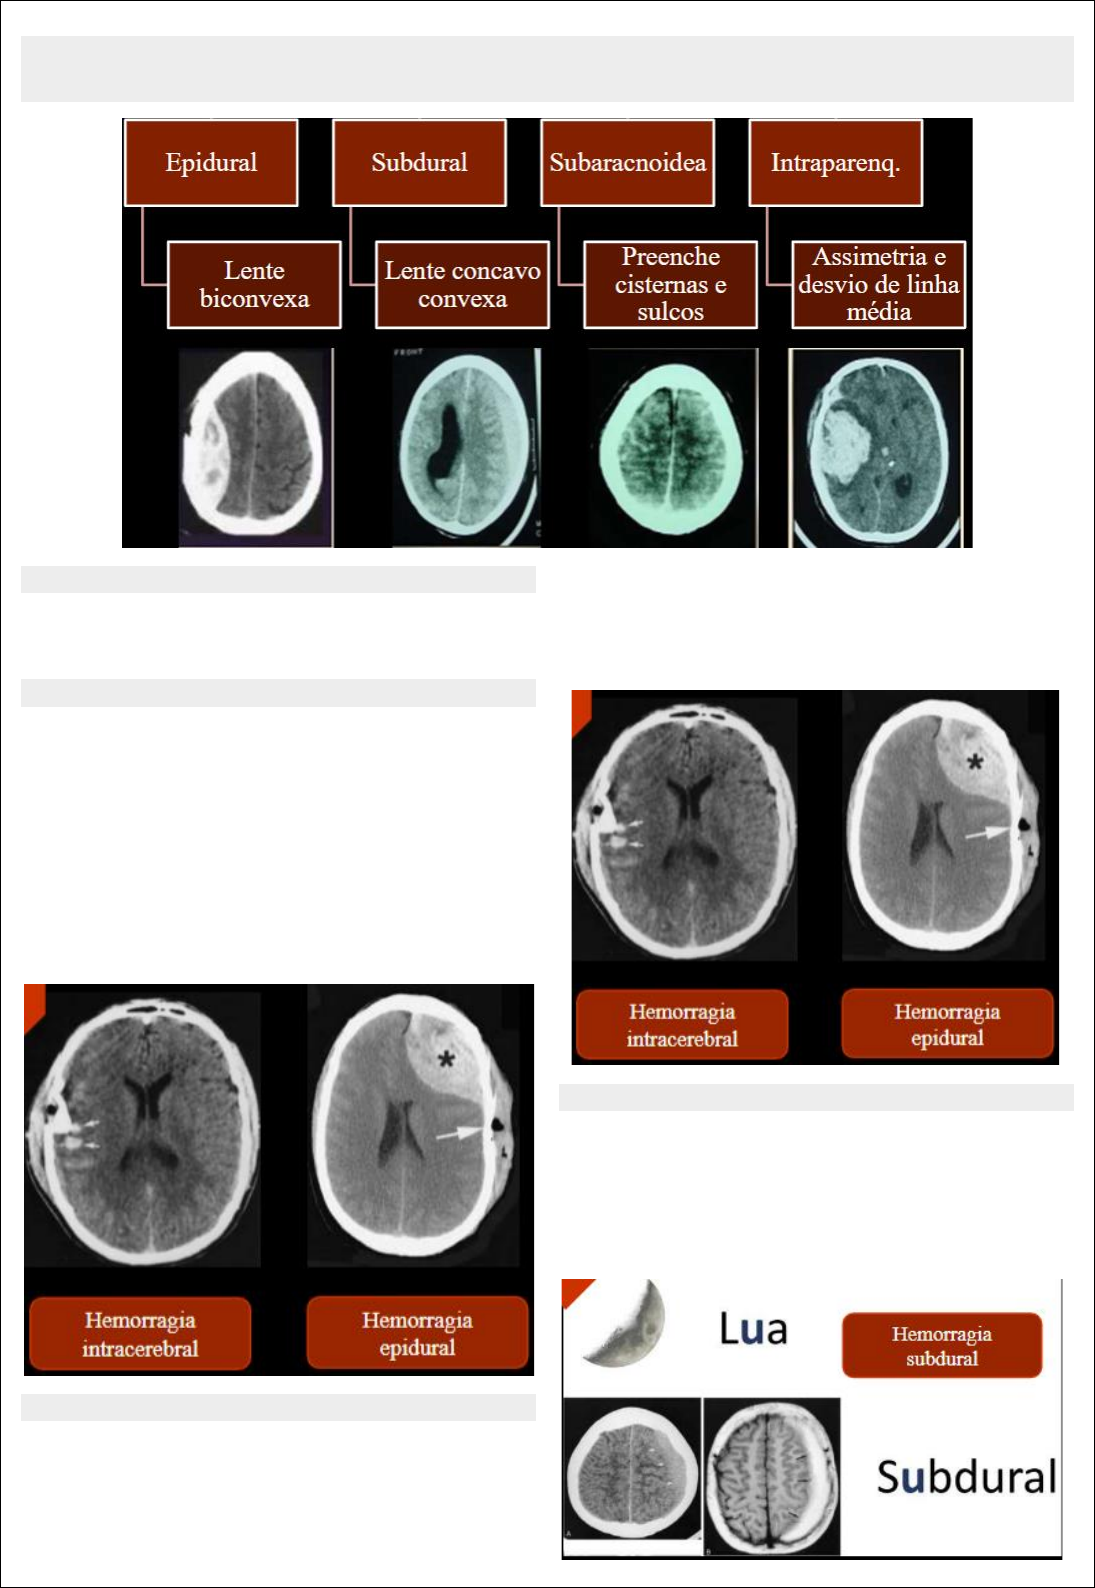

HEMORRAGIA

HEMATOMA INTRACEREBRAL

Os hematomas intracerebrais tendem a apresentar menos

edema circundante do que as contusões corticais, pois

representam sangramento em áreas cerebrais

relativamente normais. A maioria dos hematomas

intracerebrais se localiza na substância branca da região

frontotemporal, embora também tenham sido descritos

nos núcleos da base. Muitas vezes, estão associados a

fraturas cranianas e outras lesões neuronais primárias,

incluindo contusões e LAD.

HEMATOMA EPIDURAL

A maioria dos hematomas epidurais se localiza na região

temporal ou temporoparietal, embora também possam

surgir hematomas nas regiões frontal e occipital.

Hematomas epidurais venosos são menos comuns que

arteriais e tendem a ocorrer no vértice, na fossa posterior

ou no aspecto anterior da fossa craniana média.

Geralmente, hematomas venosos ocorrem como resultado

da ruptura dos seios venosos durais.

HEMATOMA SUBDURAL

Tipicamente, é de origem venosa, resultado do estiramento

ou rompimento de veias corticais que atravessam o espaço

subdural em seu caminho até os seios durais. Pode também

ser consequência do rompimento de ramos penetrantes de

artérias cerebrais superficiais.

HEMORRAGIA SUBARACNÓIDEA

É comumente encontrada em lesões cranianas; porém,

raramente é substancial o suficiente para causar efeito

expansivo significativo. A hemorragia resulta do

rompimento de pequenos vasos subaracnoides ou da

extensão até o espaço subaracnoide de uma contusão ou

hematoma. Na TC, a hemorragia subaracnóidea aparece

como áreas de alta atenuação nas cisternas e nos sulcos.